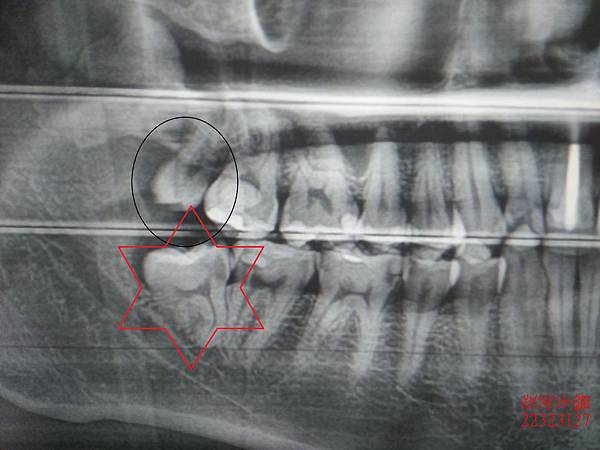

患者右側上、下各有一顆智齒,在拔除上方智齒後,傷口輕微不舒服。

再另排時間來拔除難纏的下顎智齒。

此顆牙齒由x光片看就有牙根彎曲且看似聚合的現象。